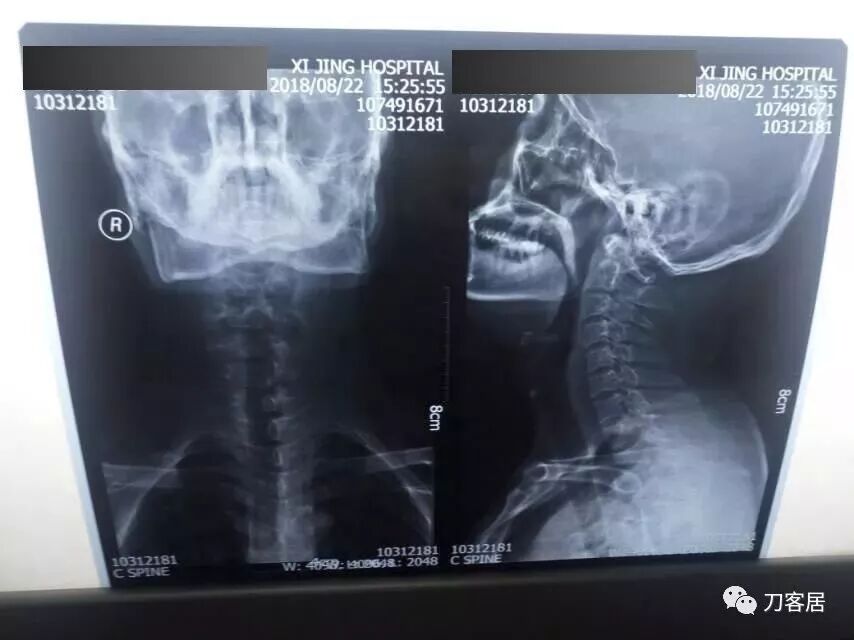

拍片子时,如果一张片子上有两张图像的时候,合起来拍一张(图15),分开再各拍一张(图16,图17)

图15